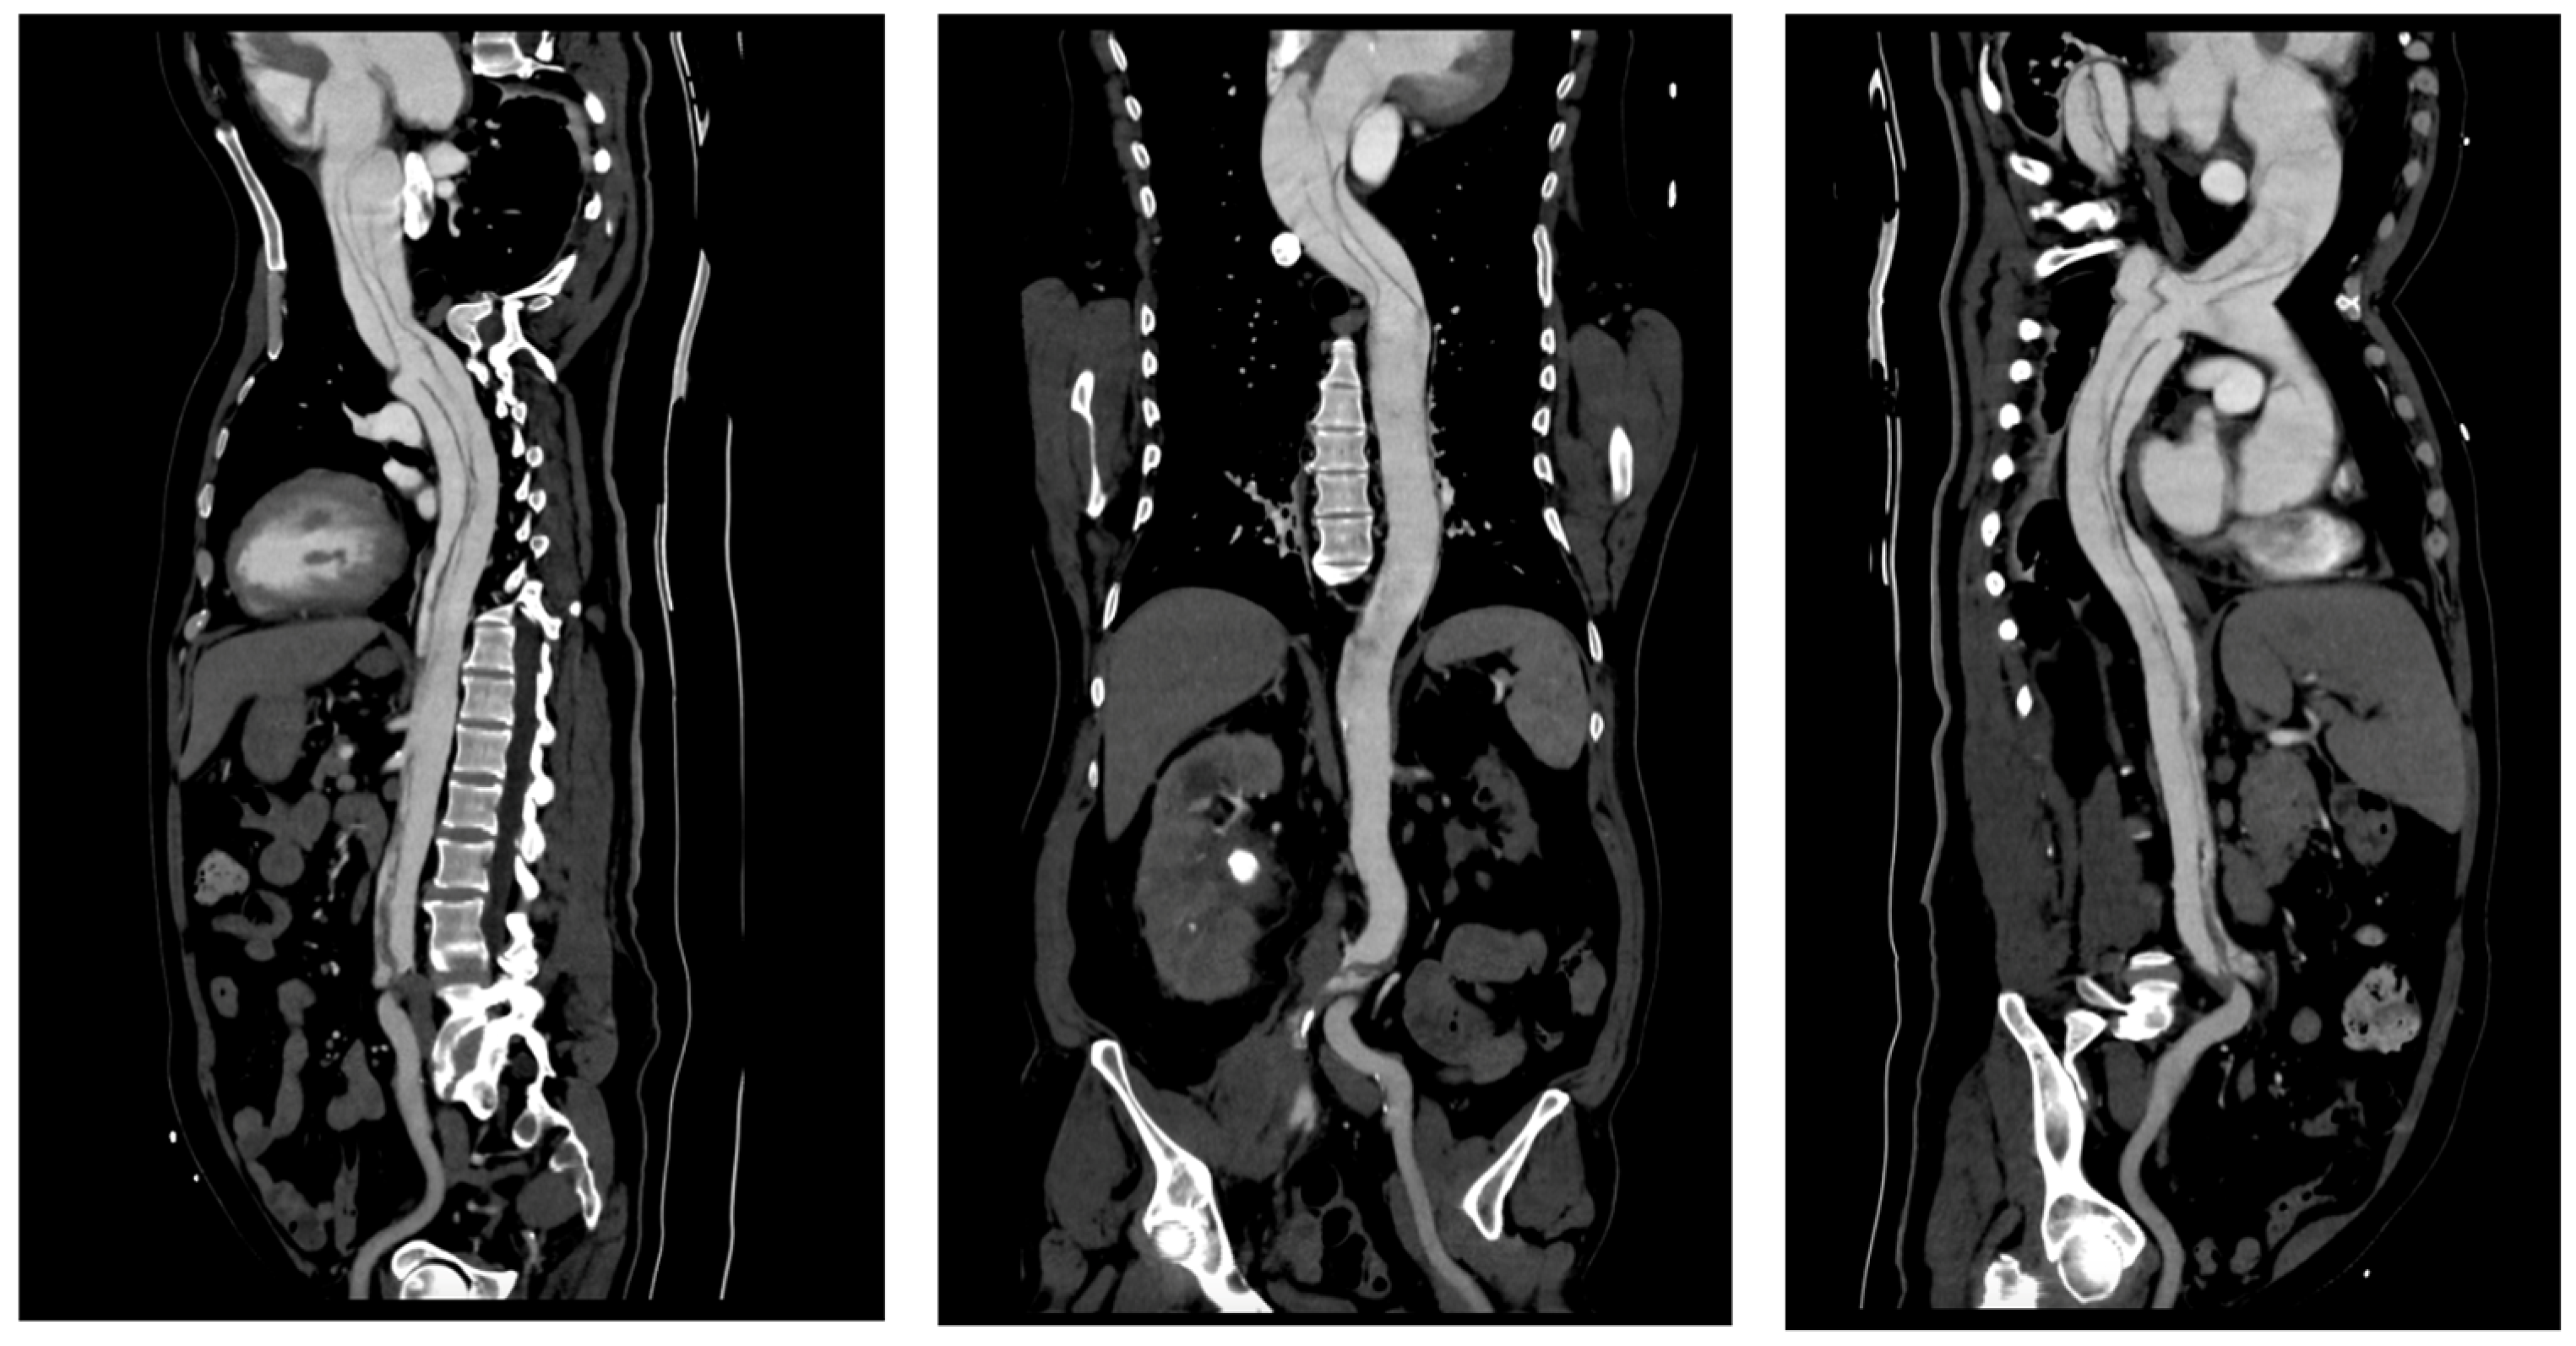

Imaging is essential for the diagnostic confirmation of aortic dissection. All patients received thoracic CTA and TTE. In the radiological evaluation of patients with aortic pathologies, precise measurements of the aortic lumen play a crucial role in assessing disease severity and planning interventions. Using true perpendicular sections, accurate diameters of the ascending and descending aorta were obtained. The following images (Figure 4) demonstrate this approach and provide representative measurements for reference.

Figure 4. Radiological measurements of the aortic lumen using perpendicular sections in a patient with aortic pathology: (a) axial view showing key diameters at different levels: ascending aorta (4.93 cm), descending aorta (2.99 cm), and distal descending aorta (3.88 cm; (b) the cross-sectional plane used for accurate measurements (4.96 cm); (c) coronal reconstruction illustrating the orientation of the imaging planes relative to the aortic arch and descending aorta, ensuring perpendicular alignment for precise dimensional assessment. These measurements are critical for diagnosing and monitoring the progression of aortic diseases and planning surgical or interventional management.